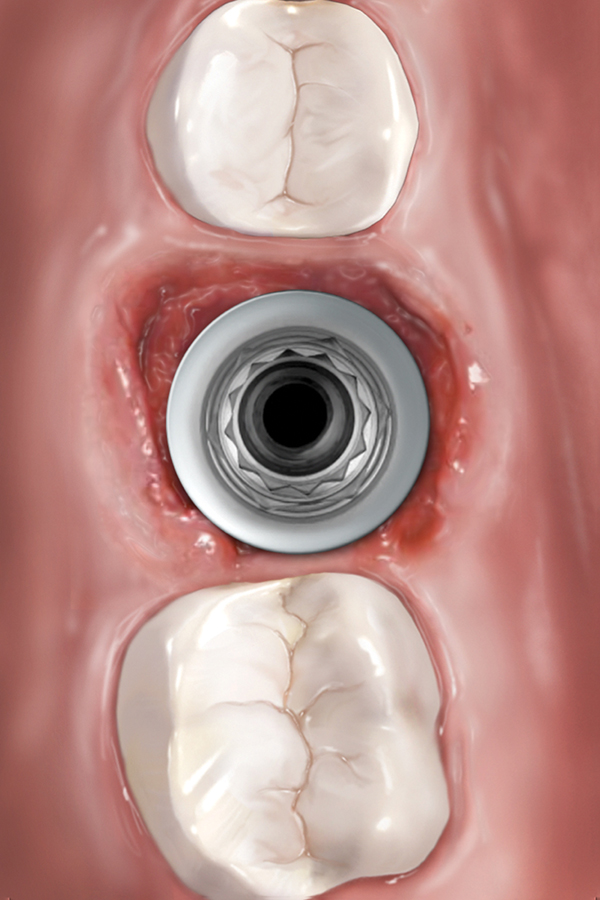

Tooth Cusp Mandibular Molars

Tooth Cusp Mandibular Molars